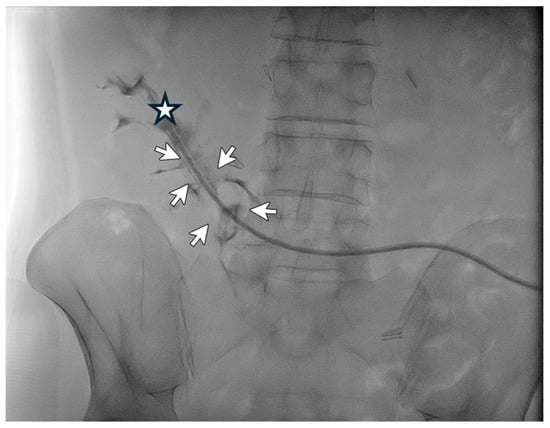

A 79-year-old female patient in peritoneal dialysis for 14 months for diabetic kidney disease was diagnosed with malfunction of the peritoneal catheter with inflow and outflow problems. The patient was thus subjected to catheterography, which showed the tip ending stuck against the right lumbar region (Figure 4). The guidewire manipulation did not manage to reposition the catheter in the pelvis, as the catheter was probably blocked by consolidated adhesions anchoring it to the abdominal side wall. No complication was reported. The patient dropped out of peritoneal dialysis and switched to hemodialysis by choice.

Figure 4. Use of the guide (Wire M—stiff type angled) to reposition the catheter tip (Life 14 01475 i002)—pointing against the right lumbar region—under radioscopic guidance.